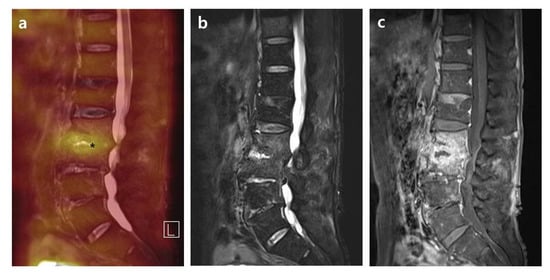

2.3.2. Distribution Patterns of FDG Uptake on FDG-PET, Contrast Enhancement on T1-Weighted Contrast MRI, and High Signal on T2-Weighted Fat Saturation MRI in PVO Lesion

- Grade I: Activities on the bone, soft tissue, and epidural space with intensity lower than or comparable to the reference.

- Grade II: Limited activities on the margin or bulk of a destroyed disc and endplates rather than the bone, soft tissue, and epidural space with overall higher intensity than the reference.

- Grade III: Significantly increased activities on overall bone and soft tissue than the reference.